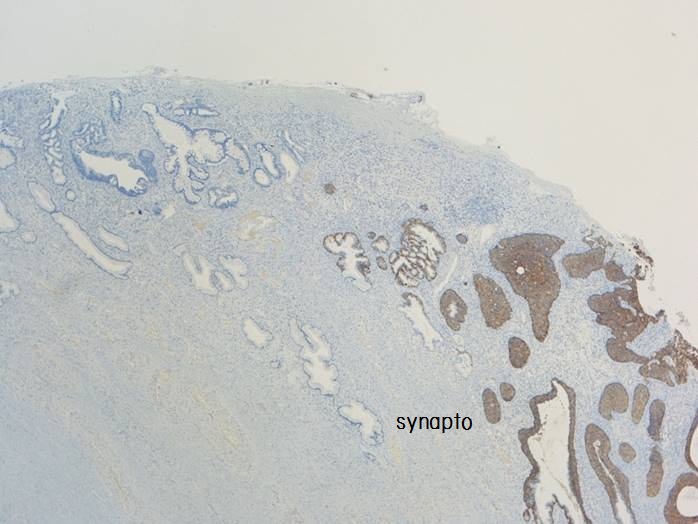

子宮頸部のSCJにおいてクロマチン増量を示す異型上皮が明瞭な

腺管構造や充実性胞巣構造を形成し増生していた。充実性増生を示す成分はN/C比や核分裂像が目立ち、免疫染色ではsynaptophysin、chromogranin A、CD56が陽性であり神経内分泌分化が示唆された。以上の所見より、神経内分泌癌成分を伴う腺癌と診断された。面積的には腺癌成分が8割で神経内分泌癌成分は2割であった。腺癌成分で微小浸潤がみられたが神経内分泌癌成分はin situであった。

腺管構造や充実性胞巣構造を形成し増生していた。充実性増生を示す成分はN/C比や核分裂像が目立ち、免疫染色ではsynaptophysin、chromogranin A、CD56が陽性であり神経内分泌分化が示唆された。以上の所見より、神経内分泌癌成分を伴う腺癌と診断された。面積的には腺癌成分が8割で神経内分泌癌成分は2割であった。腺癌成分で微小浸潤がみられたが神経内分泌癌成分はin situであった。